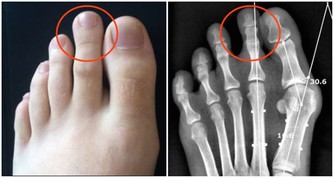

另外,護肝保健操也有裨益,做法是—— 第一步,揉大敦穴。盤腿端坐,赤腳,用左手拇指按壓右腳大敦穴(腳大趾甲根部外側),左旋按壓15次,右旋按壓15次。然後用右手按壓左腳大敦穴,手法同前。

第二步,按太衝穴。盤腿端坐,用左手拇指按右腳太衝穴(腳背第一、二趾骨之間),沿骨縫的間隙按壓並前後滑動,做20次。然後用右手按壓左腳大敦穴,手法同前。